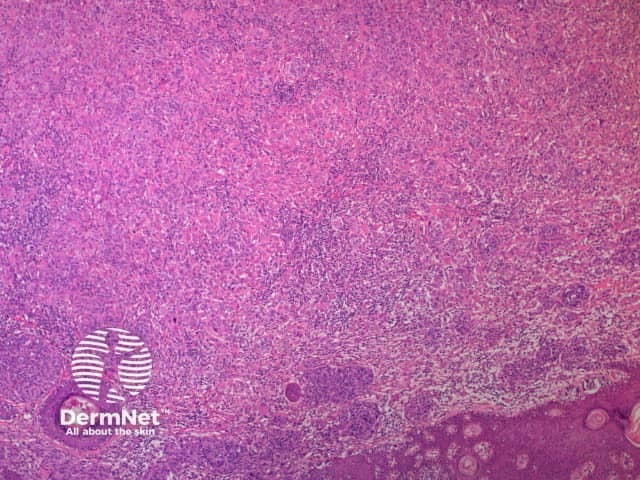

A BAP1-inactivated melanocytic tumour is predominantly based in the dermis (figure a), but it may be combined with a smaller adjacent junctional area that has more regular naevoid cells (which represents a common naevus component).

a. Low-power view, haematoxylin and eosin stain

BAP1-deficient lesion. Male 14, back with a pedunculated lesion. Images supplied by Professor Richard Scolyer.